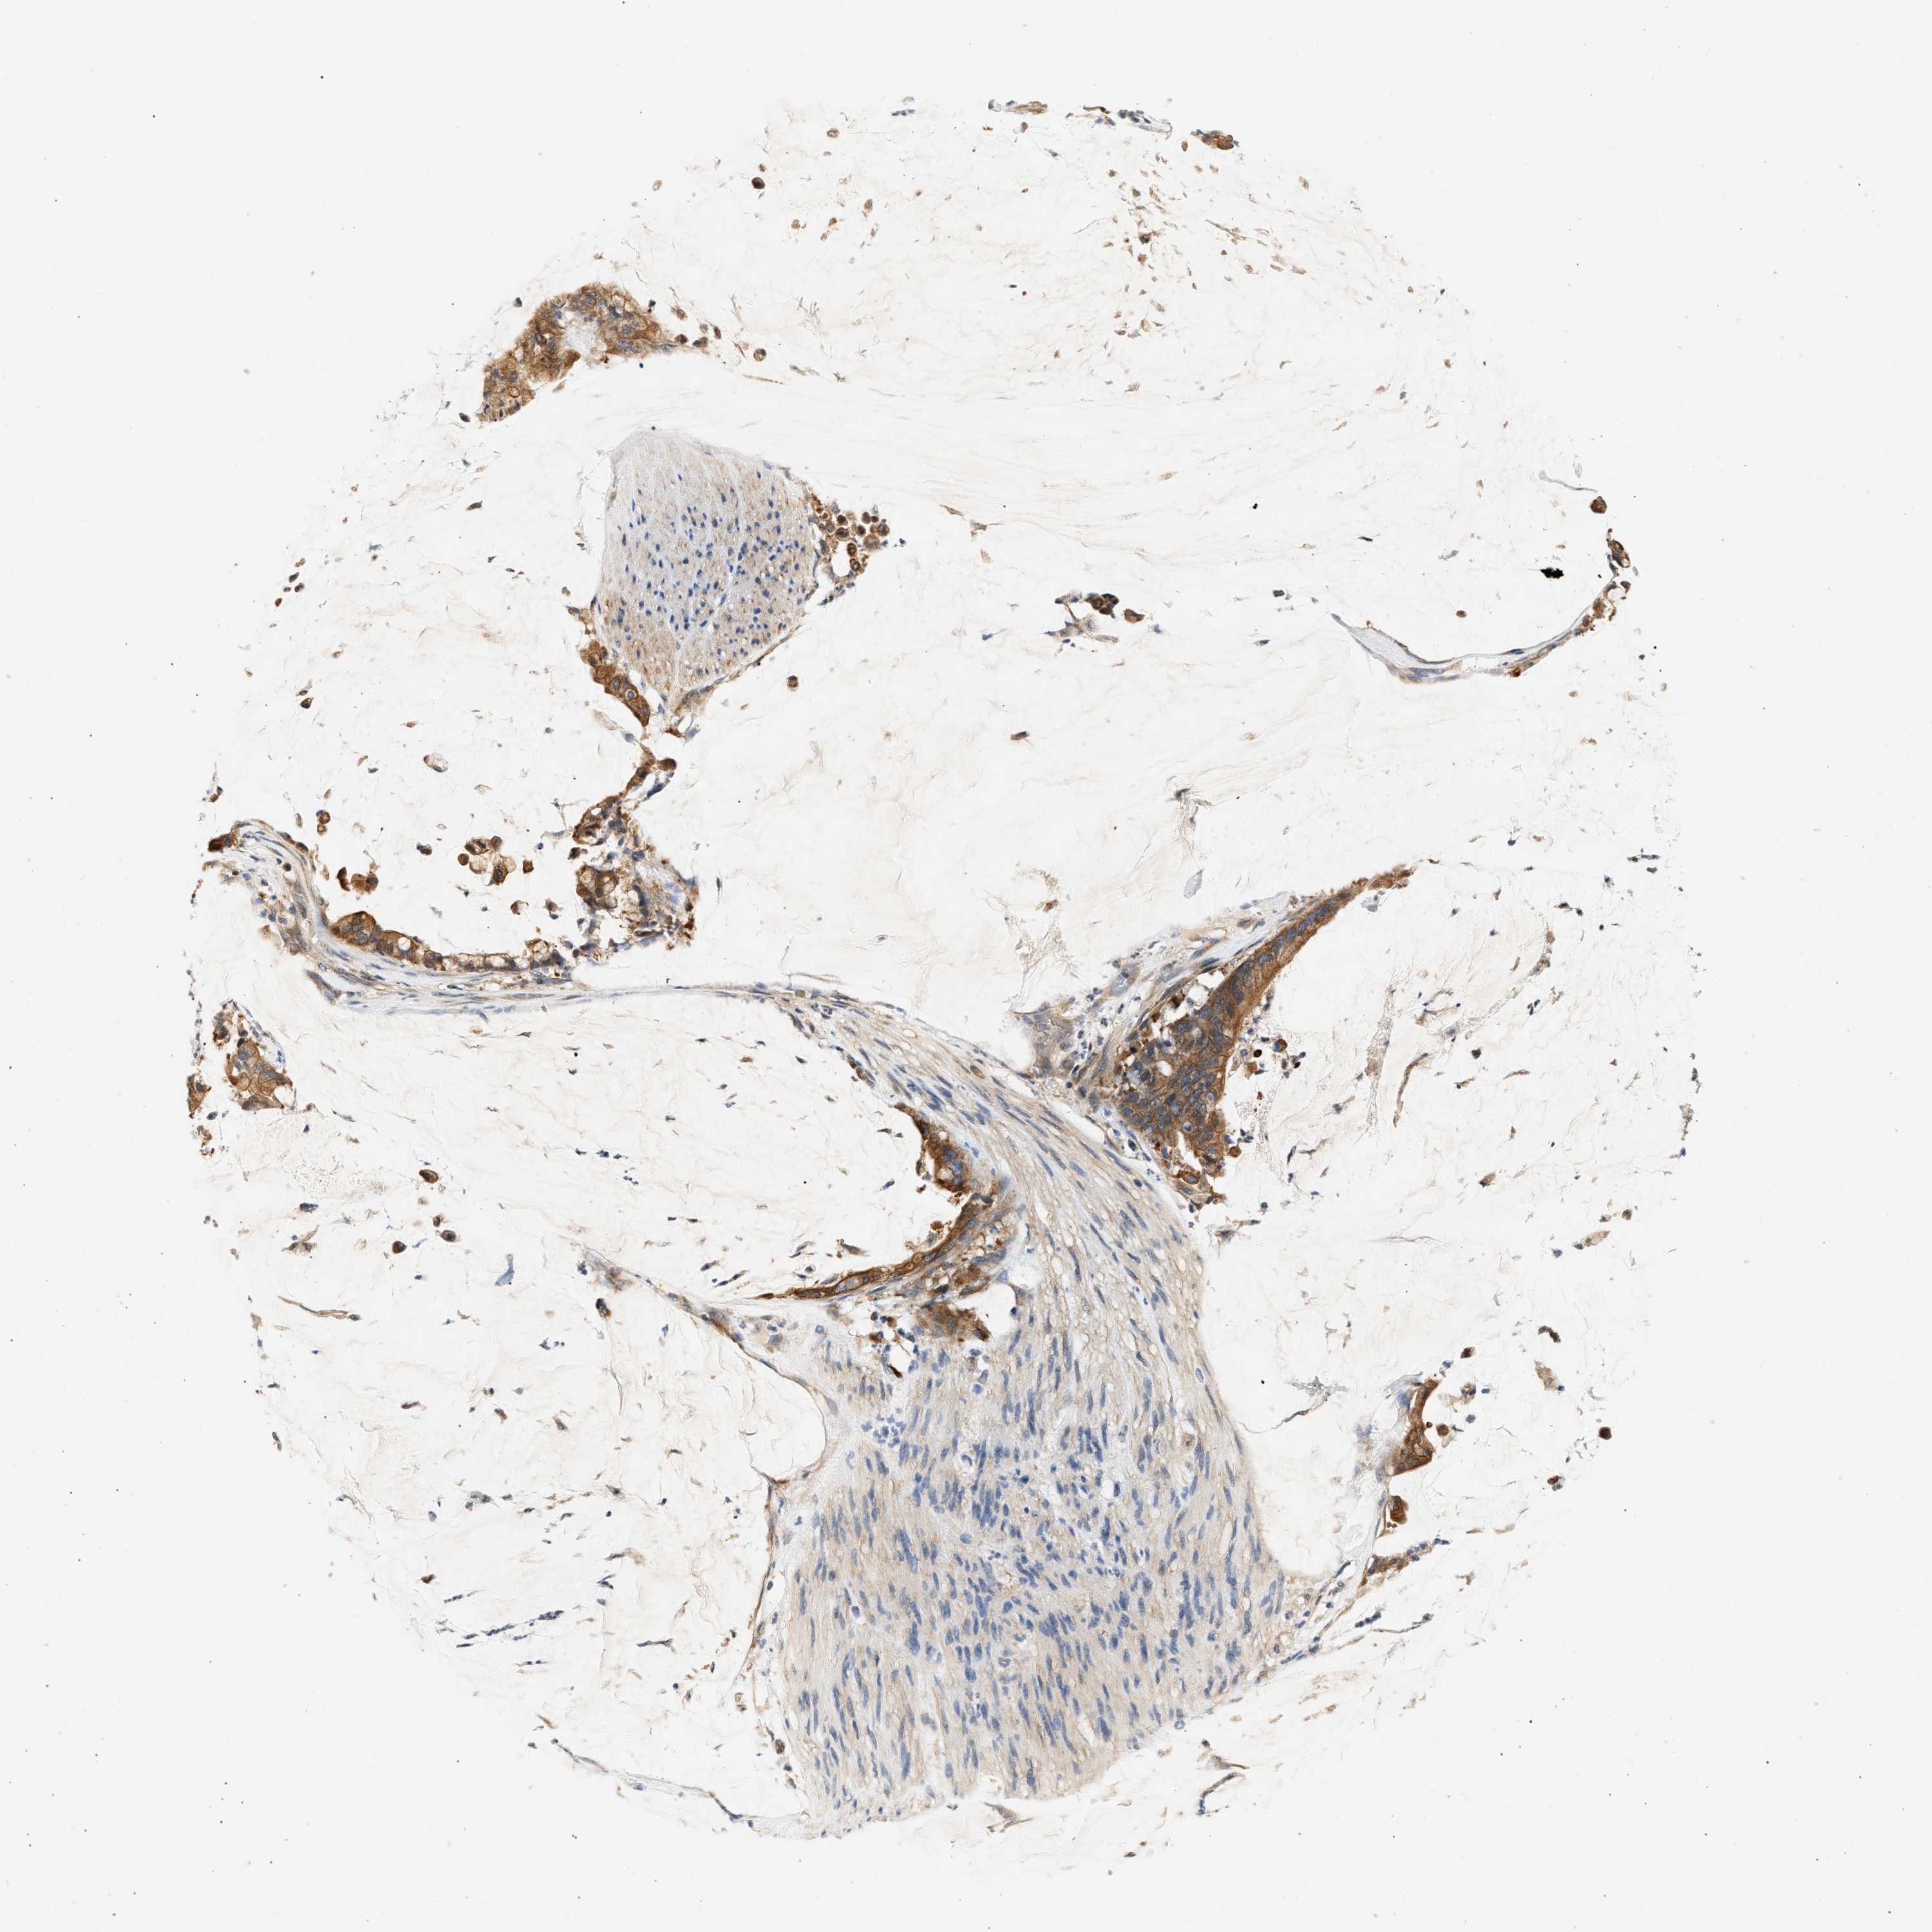

PANCREATIC CANCER - Protein expressioni

A mouse-over function shows sample information and annotation data. Click on an image to view it in a full screen mode. Samples can be filtered based on level of antibody staining by selecting one or several of the following categories: high, medium, low and not detected. The assay and annotation is described here.

Note that samples used for immunohistochemistry by the Human Protein Atlas do not correspond to samples in the TCGA dataset.

Antibody stainingi

Antibody staining in the annotated cell types in the current human tissue is reported as not detected, low, medium, or high, based on conventional immunohistochemistry profiling in selected tissues. This score is based on the combination of the staining intensity and fraction of stained cells.

Each image is clickable and will lead to virtual microscopy that enables deeper exploration of all samples and also displays staining intensity scores, fraction scores and subcellular localization as well as patient and tissue information for each sample.

Antibody HPA019340

Antibody HPA019347

Staining

High

Medium

Low

Not detected

Intensity

Strong

Moderate

Weak

Negative

Quantity

>75%

75%-25%

<25%

None

Location

Nuclear

Cytoplasmic/membranous

Cytoplasmic/membranous,nuclear

Adenocarcinoma, NOS